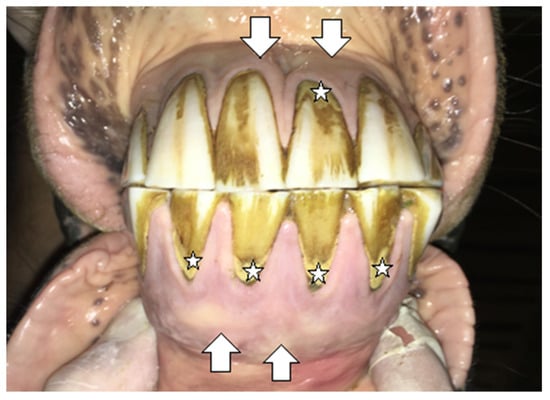

2.1.1. Case 1

2.1.2. Case 2